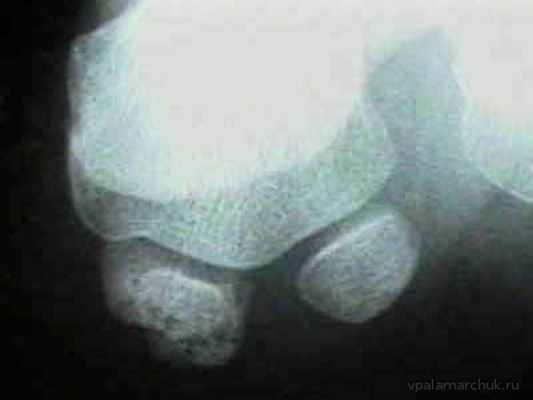

Здесь как раз выраженный сесамоидит. Отмечаются изменения в трабекулярной структуре кости

Диагностика обычно не несет каких-то проблем. При осмотре выявляется боль с подошвенной поверхности плюснефалангового сустава большого пальца. Обязательно проводится рентгенография, чтобы отличить такие заболевания как подагра, артроз, подвывих большого пальца при поперечном плоскостопии. А также важное — перелом сесамовидной кости имеет сходные симптомы.

Перелом сесамовидной кости. Нужно помнить, что иногда выявляется «дольчатая» сесамовидная кость. Обычно состоящая из двух (бывает больше) элементов. Но в таком случае на рентгенограмме видны ровные и гладкие края «долек»